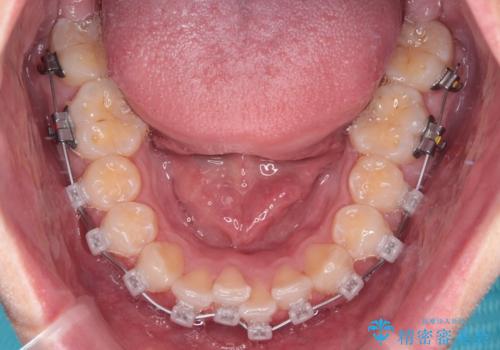

- 矯正装置

- メタルブラケット

・上顎左右の第二大臼歯が頬側へ転移し、シザーズバイト(scissors bite)の状態

・上顎左側第二小臼歯が90度捻転しており、噛み合わせに影響

・奥歯のシザーズバイト改善には、口蓋側にアンカースクリュー(TAD)を設置し、矯正用ゴムで内側に牽引

・捻転した第二小臼歯は、ワイヤーと矯正用ゴムの力を用いて正しい位置へ回転移動